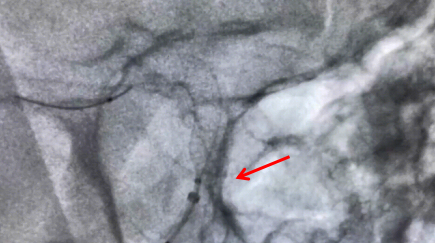

近日,我院神经外科成功实施重庆市第二例、璧山区首例Surpass Evolve血流导向密网支架介入手术,标志着我院颅内动脉瘤治疗技术实现新突破,也代表我院神经外科介入技术再上新台阶。

近日,重庆医科大学附属璧山医院(重庆市璧山区人民医院)心血管内科成功为1名难治性高血压患者实施了区内首例一站式分侧肾上腺静脉取血术+肾动脉造影术。